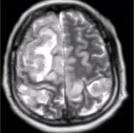

- [材料题] 女性,产后癫痫、剧烈头痛1天,意识障碍3小时。MRI显示如下图。

- 多项选择题1.关于MRI表现的描述,正确的是

A、双侧额叶、顶叶皮质肿胀,脑沟变浅

B、病变同时累及皮质及皮质下白质

C、上矢状窦流空信号消失

D、病变占位效应明显

E、病变信号均匀

F、病变邻近脑膜增厚